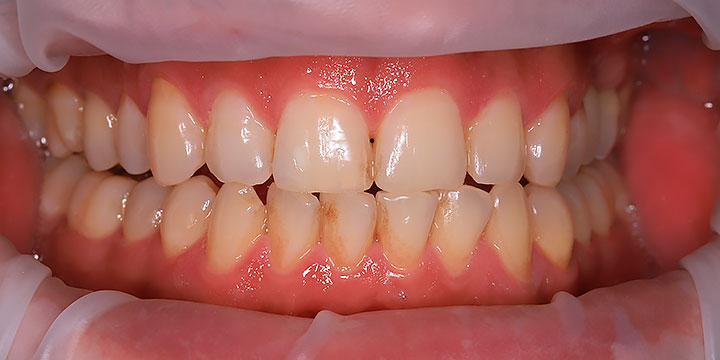

Ходили с мужем на гигиеническую чистку к доктору Алексею. Расположил с первой секунды, заботливо проговаривал каждое свое действие, включил фильм, сделал фото до/после. Процедура сама по себе не из приятных, но конкретно эта оставила только приятные впечатления????